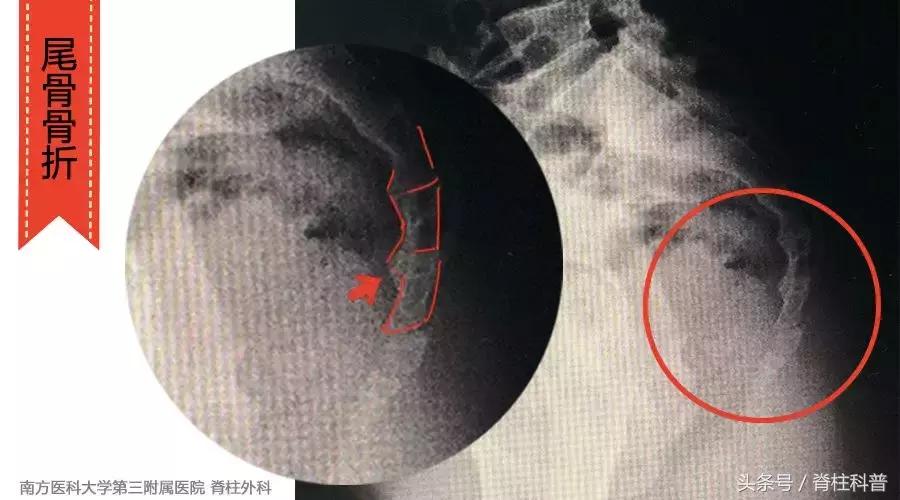

这样的疼痛方式,最常见的原因就是骶尾骨陈旧性骨折。(注意这里说的是最常见原因)

这种骨折一般是从前有摔伤史(就是一屁股坐地上,广州话说的是“㩐亲条尾龙骨”)。这类陈旧性的骶尾骨骨折,一般不需要特殊治疗。注意坐着的时候,稍稍向前靠即可。疼痛剧烈的,就吃点止痛药,抹些药膏。

尾骨陈旧性骨折